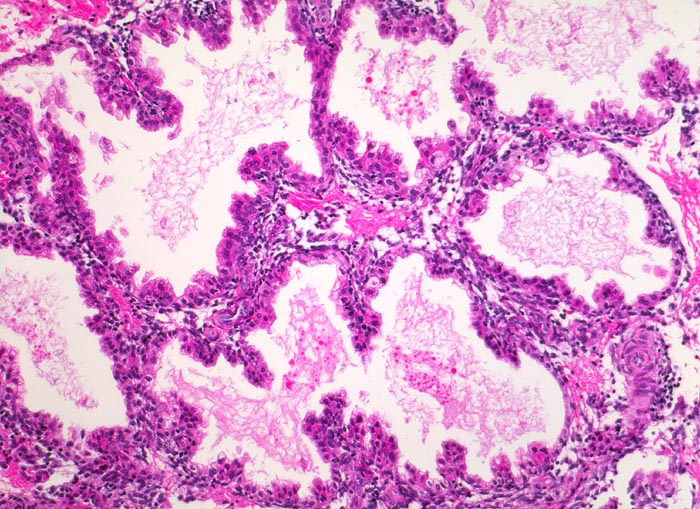

Morphologische Merkmale:

• Vergrösserte Plazentarzotten mit hydropischem Zottenstroma.

• Vereinzelt Zytotrophoblasteinschlüsse im Stroma.

• Vorwiegend einschichtiges Zytotrophoblastepithel ohne Atypien und mehrkerniger Synzytiotrophoblast. Physiologische polare Trophoblastproliferate.

• Kein Embryo.

• Keine Anteile der Dezidua.